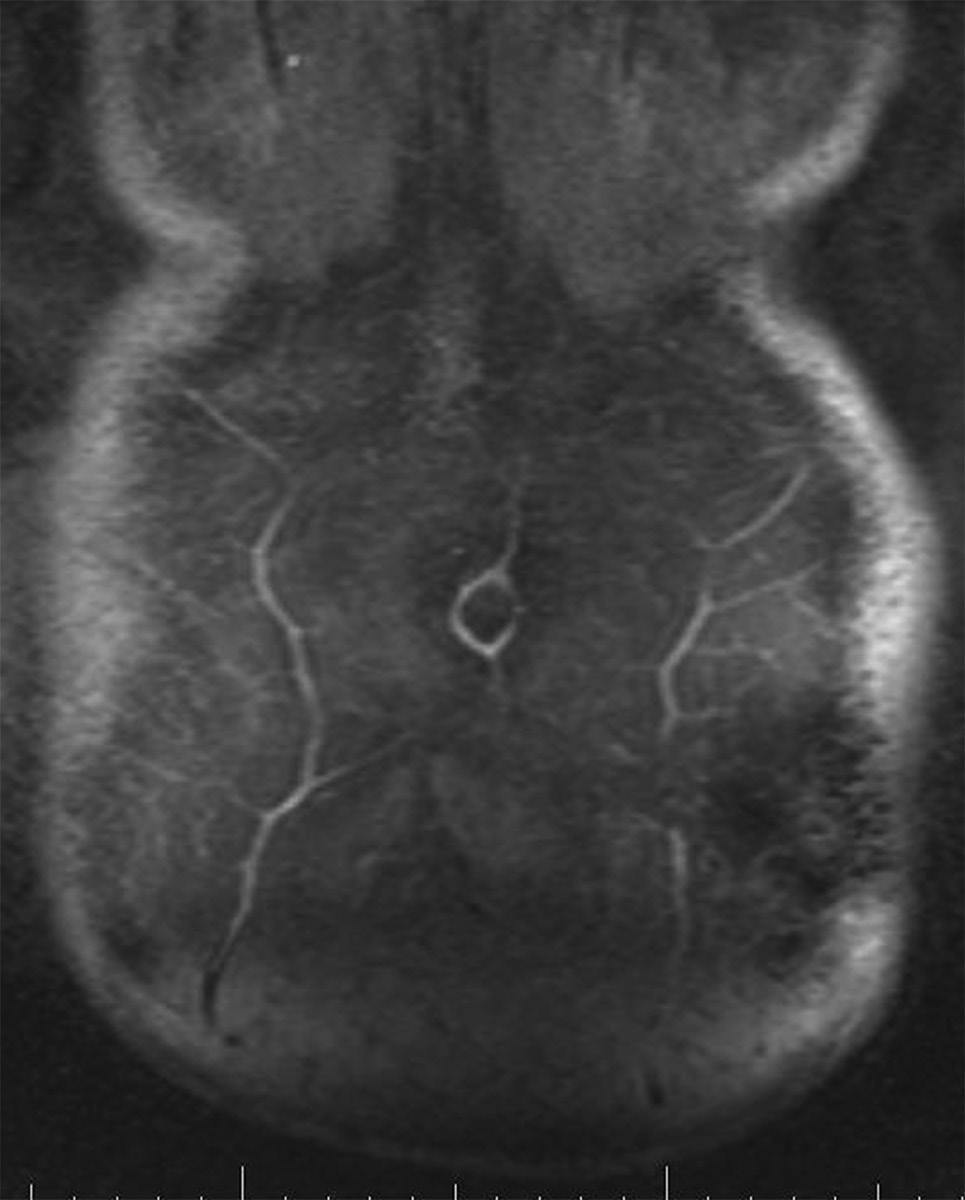

s The superior epigastric artery (SEA) and deep inferior epigastric artery (DIEA) lie on the posterior aspect of the rectus abdominis muscles and supply the muscle and overlying skin and subcutaneous tissue through musculocutaneous perforators (Fig. 1.9).

s A study by Saber et al. (2004) provided guidelines for location of the epigastric vessels based on computed tomography scan data in 100 patients. At the xiphoid process, the SEA was 4.41 ± 0.13 cm from the midline on the right and 4.53 ± 0.14 cm from the midline on the left. Midway between the xiphoid and umbilicus, the SEA was 5.50 ± 0.16 cm from the midline on the right and 5.36 ± 0.16 cm from the midline on the left. At the umbilicus, the epigastric vessels were 5.88 ± 0.14 cm from the midline on the right and 5.55 ± 0.13 from the midline on the left. Midway between the umbilicus and symphysis pubis, the inferior epigastric artery was 5.32 ± 0.12 cm from the midline on the right and 5.25 ± 0.11 cm from the midline on the left. At the symphysis pubis, the inferior epigastric artery was 7.47 ± 0.10 cm from the midline on the right and 7.49 ± 0.09 cm from the midline on the left.

s The DIEA is dominant in the vascular supply of the abdominal muscles compared with the SEA. The two arborizing vascular systems converge within the rectus abdominis muscle at a point between the xiphoid process and umbilicus. In a study by Taylor (2003), the mean diameter of the DIEA at its point of origin was 3.4 mm compared with 1.6 mm for the SEA, perhaps explaining the dominant arterial supply of the DIEA.